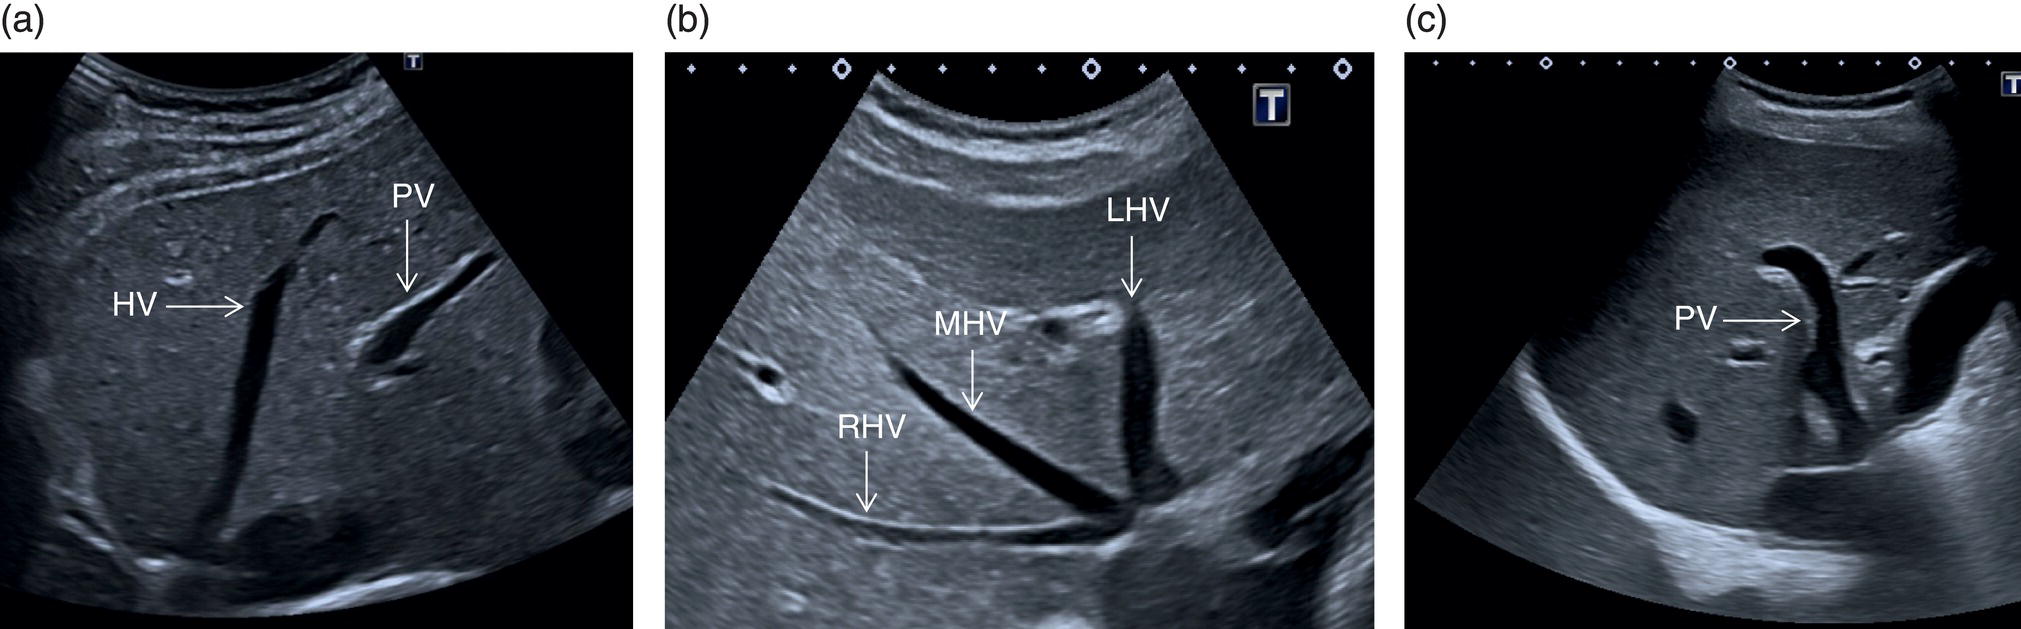

The right liver lobe includes segments V–VIII, which should be assessed in both the LS and TS planes via a subcostal and intercostal approach, as shown in Figures 3.24–3.26 (Video 3.5). Start again by keeping the probe in the epigastric region in a TS view. By angling upwards, you will visualise the most cranial liver segments (from left to right of the patient will be segment II, IV, VIII) and you will image part of the heart, eventually excluding or highlighting the presence of a pericardial effusion. Then, remaining in the subcostal scanning position, turn the probe oblique (rotating anticlockwise) and slowly angle downwards, making small adjustments as required. By doing so you will visualise the confluence of the three hepatic veins and the IVC from two slightly different angles, with the oblique scan favouring the visualisation of the right hepatic vein (Figure 3.24) (Video 3.5). Maintaining the same probe position and slowly moving downwards, you will visualise first the GB and left branch of the PV and then, eventually turning the patient left side down and making small adjustments, you will visualise the PV crossing and ‘dividing’ the liver in a cranial and caudal region (Figure 3.25) (Videos 3.6 and 3.7). Bear in mind that according to body habitus, when sweeping downwards the PV might appear before the GB or viceversa. Representative images of the right lobe should also be obtained intercostally, moving the probe from one intercostal space to another angling upwards and downwards in order to have a complete view from each angle (Video 3.5). A representative image of the liver with the right kidney is important to allow comparison of its echogenicity to the cortex of the right kidney to diagnose or exclude steatosis. This image can be obtained in the LS plane, starting along the mid‐clavicular line and sweeping outwards (laterally) until the kidney is visualised, or intercostally in case of bowel gas interference (Figure 3.26) (Video 3.8).

The HA has echogenic walls, it runs anteriorly to the PV and posteriorly to the CBD, and its normal calibre at the hepatic hilum measures up to 3 mm in diameter (Figure 3.34). The hepatic veins have thinner and less echogenic walls [8] and have a straighter and linear course compared to the portal venous system. Although the measurement of the hepatic veins is usually not performed on a routine basis, the cut‐off value of their calibre is approximately 8 mm, measured at about 2–3 cm from their confluence into the IVC [9]. It should be kept in mind that in lean subjects both IVC and hepatic veins may be more ectatic. When performing a liver ultrasound scan it is important to keep in mind that the echogenicity of both hepatic veins and PV walls changes according to the angle between the ultrasound beam and the vascular wall. The more acute is the angle of insonation, the closer it is to being parallel to the longitudinal axis of the vessel. Therefore, despite there being clear differences between the thick perivascular collagen of the portal venous system and the thin walls of the hepatic veins (Figure 3.35), if the angle of insonation is low between the ultrasound beam and the PV walls, these could appear very thin or even not be visible. On the other hand, if the angle of insonation with the hepatic veins is close to 90°, the walls will appear thick and echogenic. It is always important to keep in mind this physical principle, remembering the anatomical landmarks and tracing the vessels to their origin: the PV to the hepatic hilum and the hepatic veins to their confluence into the IVC.

The PV is formed by the confluence of the superior mesenteric vein and the splenic vein, draining the blood of the whole digestive system and spleen (Figure 3.11). Under physiological conditions the portal venous system delivers 75% of the total hepatic inflow, whereas the hepatic artery (HA) is responsible for the remaining 25%. It is important to keep in mind the physiology and pathophysiology of the hepatic blood inflow, since during the progression of liver disease, especially when cirrhosis and portal hypertension develop, the portal venous inflow is reduced while the arterial hepatic inflow is increased (See Chapter 8). The PV can be recognised on ultrasound as a tubular structure with a variable normal calibre of approximately 8–12.5 mm, with thick echogenic walls that enters the liver together with the HA at the level of the hepatic hilum. It is followed by the HA and the biliary system in its whole intrahepatic course and for a short portion in its extrahepatic tract at the level of the porta hepatis, where it is contained within the hepatoduodenal ligament. Upon entering the liver, the PV and HA divide into the left and right branches, with further divisions providing the blood supply to each of the eight main liver segments (Figure 3.12). At the periphery of the liver lobules the arterial and venous blood mix and enter the sinusoids, terminating finally in the central veins that converge to form the right (RHV), middle (MHV), and left hepatic veins (LHV) that finally drain into the IVC (Figure 3.13). It is of note that the caudate lobe is drained independently by a main or multiple small pericaval veins. Its independent venous drainage system is the reason why the caudate lobe typically hypertrophies in advanced chronic liver disease. In Budd–Chiari syndrome, this compensatory mechanism is even more pronounced, since while the main three hepatic veins are obstructed, the pericaval ones often remain patent, leading to an abnormally hypertrophied caudate lobe (See Chapter 11).